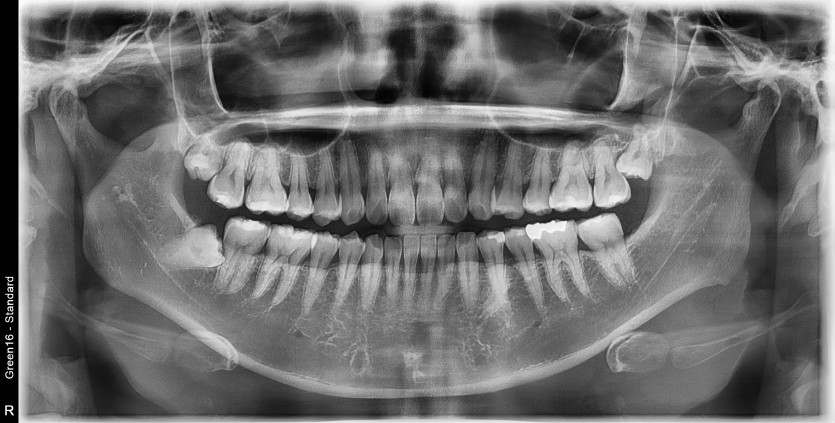

#18,48 사랑니 발치

구강 외과 전문의가 당일 발치했습니다.